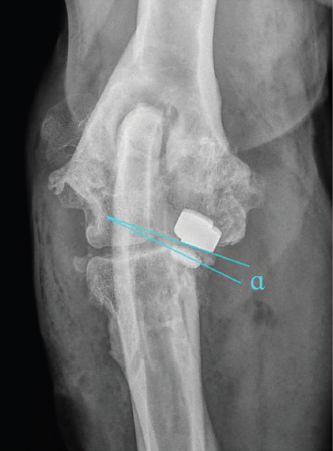

Fig. 2. Determination of implant parallelism showing a medial opening angle α=7°. First-line lies parallel to the surface of the HImpl and a second line is identical with the longitudinal axis of the elliptically projected metallic base of the UImpl.

Parallelism of the implants contact surface in the coronal plane was measured on the CrCd view. First, a line parallel to the surface of the HImpl and a second line identical with the longitudinal axis of the elliptically projected metallic base of the UImpl were drawn. The angle between those two lines is reported as medial or lateral opening angle, depending on whether the angle was open towards the medial or lateral aspect of the joint (Fig. 2).

The median deviation from true humero-ulnar implant parallelism was 10.8° (IQ: 5.5°–17.0°). In only three cases were the desired parallelism of ±1° achieved. In 41 cases, a median medial opening angle of 14.0° (IQ: 8.3°–18.0°) was found with the remaining cases having a median lateral opening angle of 3.0° (IQ: 1.8°–4.6°). The mean medio-lateral position of the HImpl was centered along the width of the humeral trochlear (50.9%; SD: 10.1%).